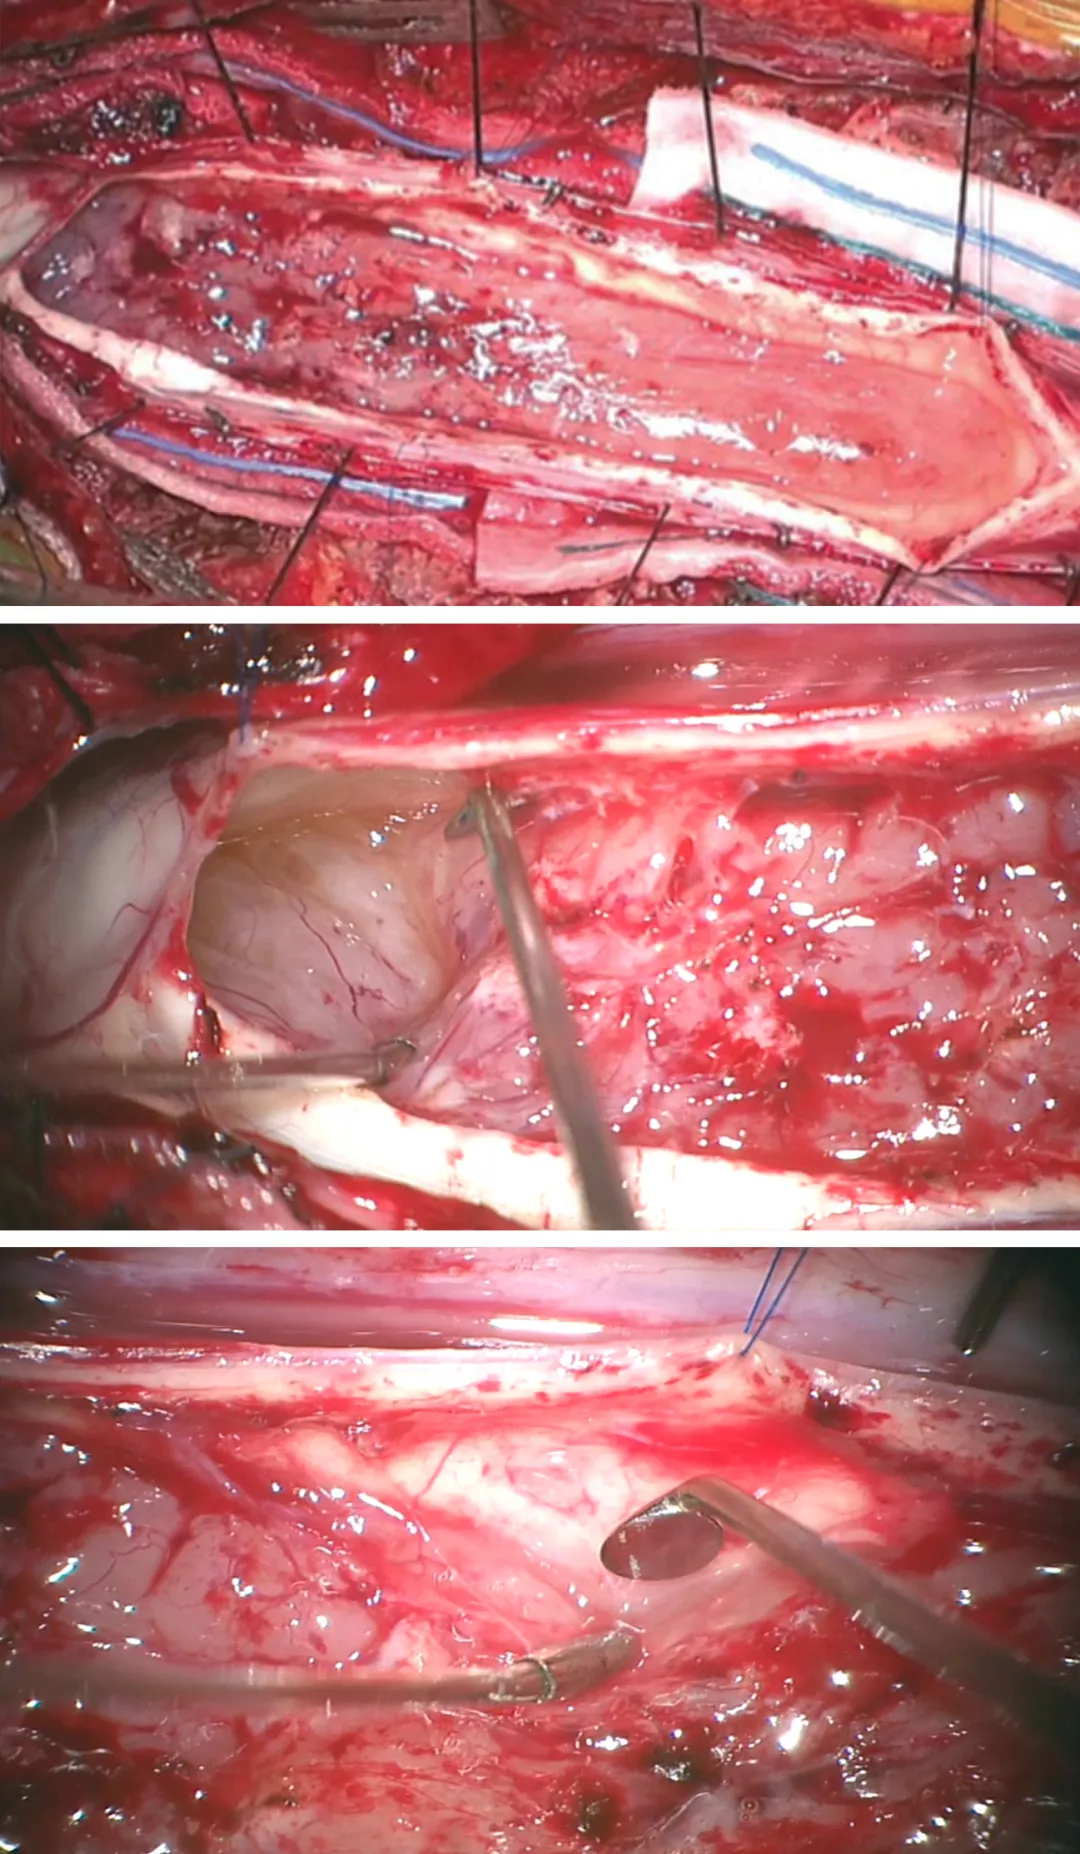

图5:图中所示为脊髓后正中沟切开脊髓切除颈髓巨大室管膜瘤的标准过程(图1显示术前图片)。仔细电凝后正中沟白质后采用蛛网膜刀切开,一把弯头吸引器或一对显微镊可用来移位或分离而不是切开后方的白质纤维(上端两幅图)。底图显示的是采用吸引器头端的特殊牵拉装置暴露肿瘤(底图)

对于体积小的髓内肿瘤可以采取整块切除,但一般体积大的肿瘤需要先进行瘤内减压或释放囊腔内容物来缩小肿瘤体积,然后再进行肿瘤切除,以免由于过度牵拉和操作损伤脊髓。

图6:采用6-0 缝线牵开软脊膜来暴露肿瘤来减少术中反复牵拉脊髓造成损伤(上图)。肿瘤上极的空洞使得瘤体与脊髓界限清晰而易于分离(中图)。底图显示采用有角度的显微剥离子将肿瘤从脊髓剥离下来(底图)。